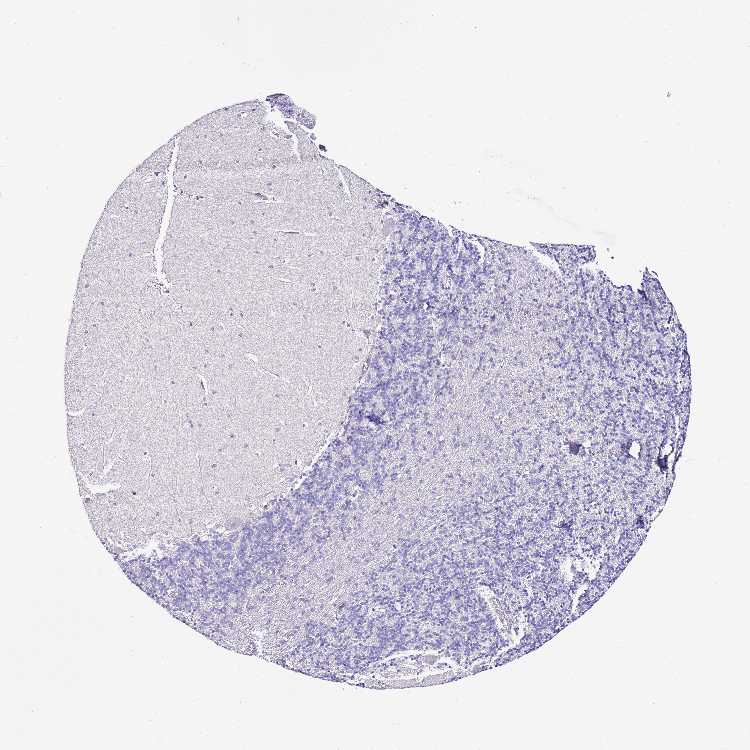

CEREBELLUM - Antibody stainingi

Antibody staining in the annotated cell types in the current human tissue is reported as not detected, low, medium, or high, based on conventional immunohistochemistry profiling in selected tissues. This score is based on the combination of the staining intensity and fraction of stained cells.

Each image is clickable and will lead to virtual microscopy that enables deeper exploration of all samples and also displays staining intensity scores, fraction scores and subcellular localization as well as patient and tissue information for each sample.

Antibody HPA047374Antibody HPA052359

Purkinje cells Not detectedNot detected

Cells in granular layer Not detectedNot detected

Cells in molecular layer Not detectedNot detected